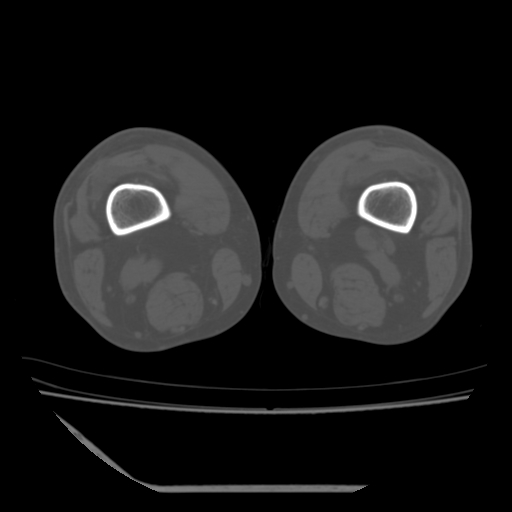

标题: CT13225:老年男性,左膝关节疼痛数月;请各位老师讨论。 [打印本页]

标题: CT13225:老年男性,左膝关节疼痛数月;请各位老师讨论。

骨质增生,骨性关节面硬化,关节积液,考虑退行性骨关节病

关节腔内少量积液,关节面退变。

双膝退变

骨质增生,骨性关节面硬化,关节间隙失常,关节积液,考虑退行性骨关节病.

这个病例诊断:退行性骨关节炎